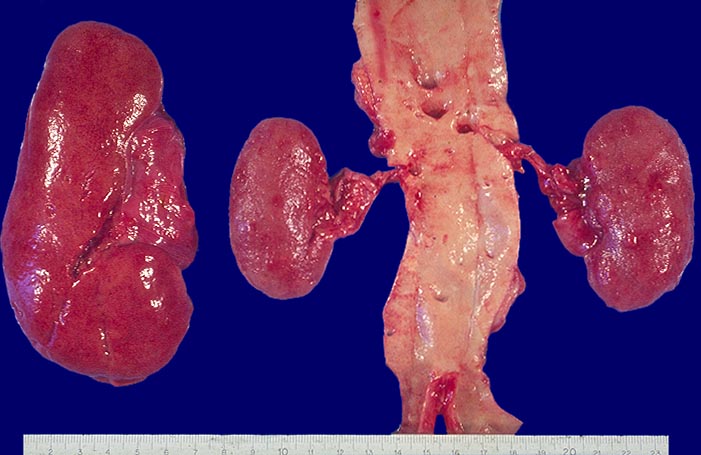

• Diskrepanz zwischen deutlich geschädigten Glomerula und weitgehend unauffälligem tubulointerstitiellem Raum.

• Vergrösserte Glomerulumanschnitte.

• Den Kapselraum ausfüllendes lobuliertes Kapillarschlingenkonvolut.

Makroskopie

Befund

Pathologischer Befund

Normalbefund